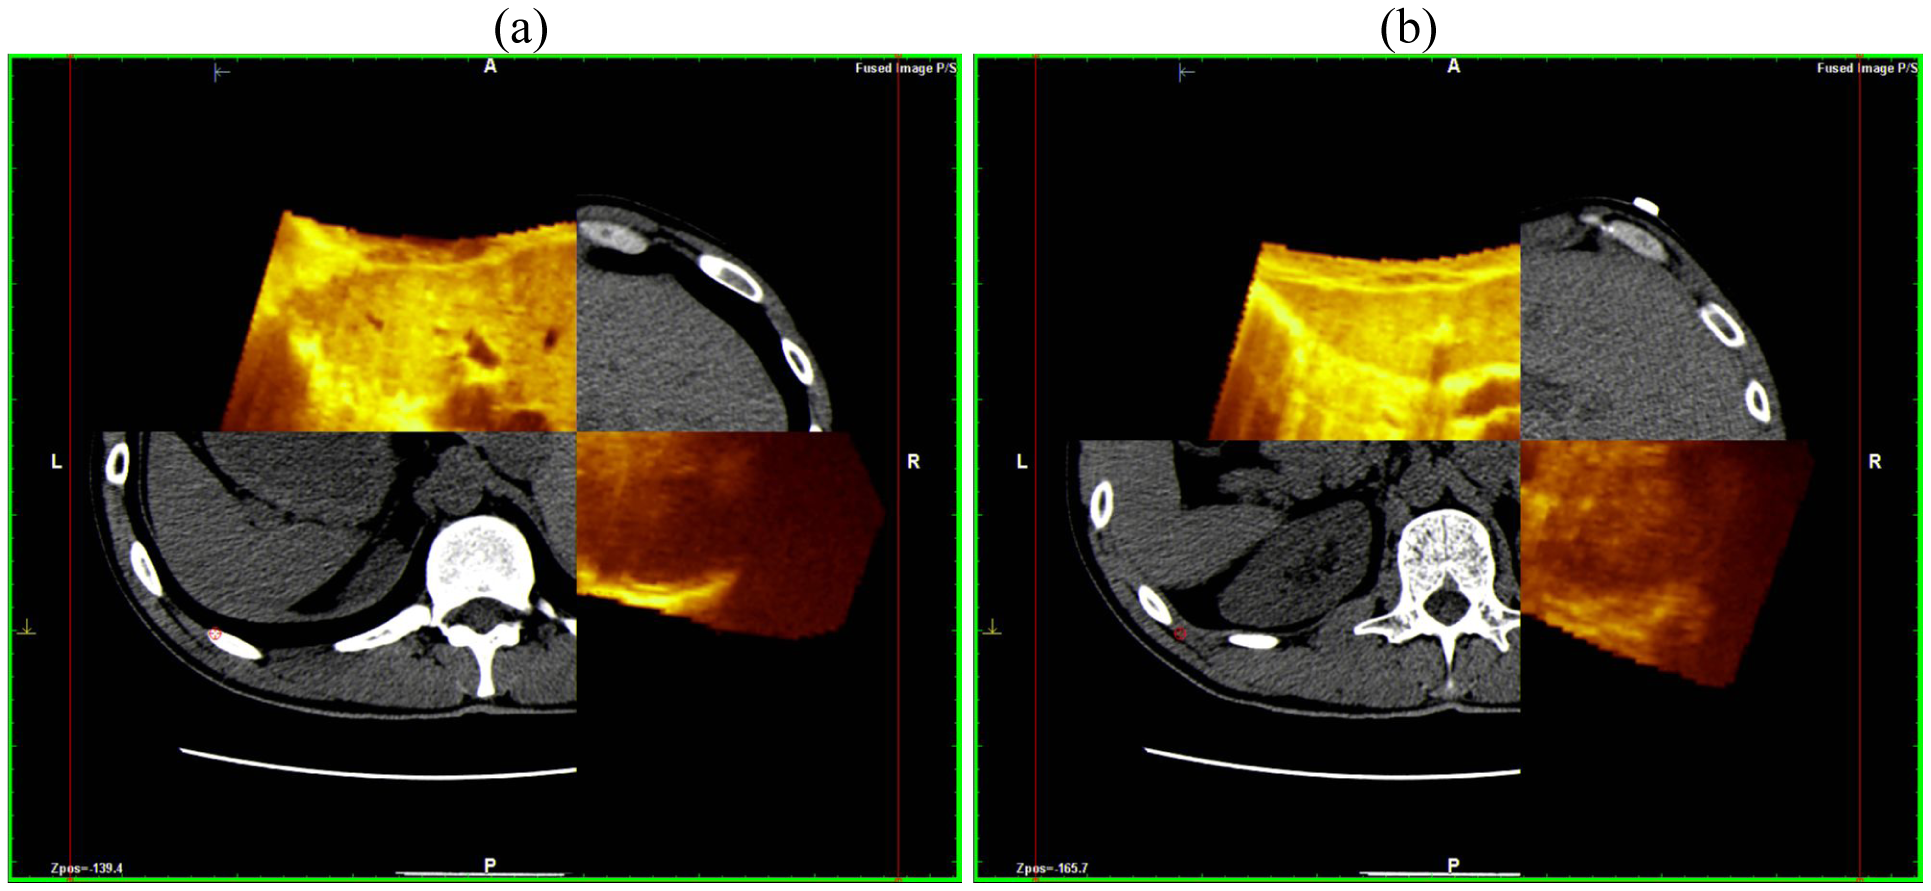

This scanning was possible both with conventional US and with contrast-enhanced US; the navigator system is furthermore able to perform a volumetric reconstruction of liver with CT scanning and to compare the two different volumes (US and CT) employing the fusion technique (Figure 3).

This superimposes each resliced layer of US and CT volumes showing both on the monitor: The post-processing fusion technique has consistently demonstrated that the CT and US 3-D reconstruction of the liver were exactly superimposable (Figure 4).

To easily perform a 3-D reconstruction of a 2-D acquisition of CEUS imaging of the whole liver, the 2-D acquisition is performed with real time scanning perpendicularly on the long-axis of the liver, for a complete 2-D image of its short-axis (Figure 2). The subsequent reconstructions of these planes show a rendered volume with a “parenchimal” aspect (Figure 5) or with a “vascular” map (Figure 6) of all the hepatic segments with an acquisition in the early arterial and in portal phase.